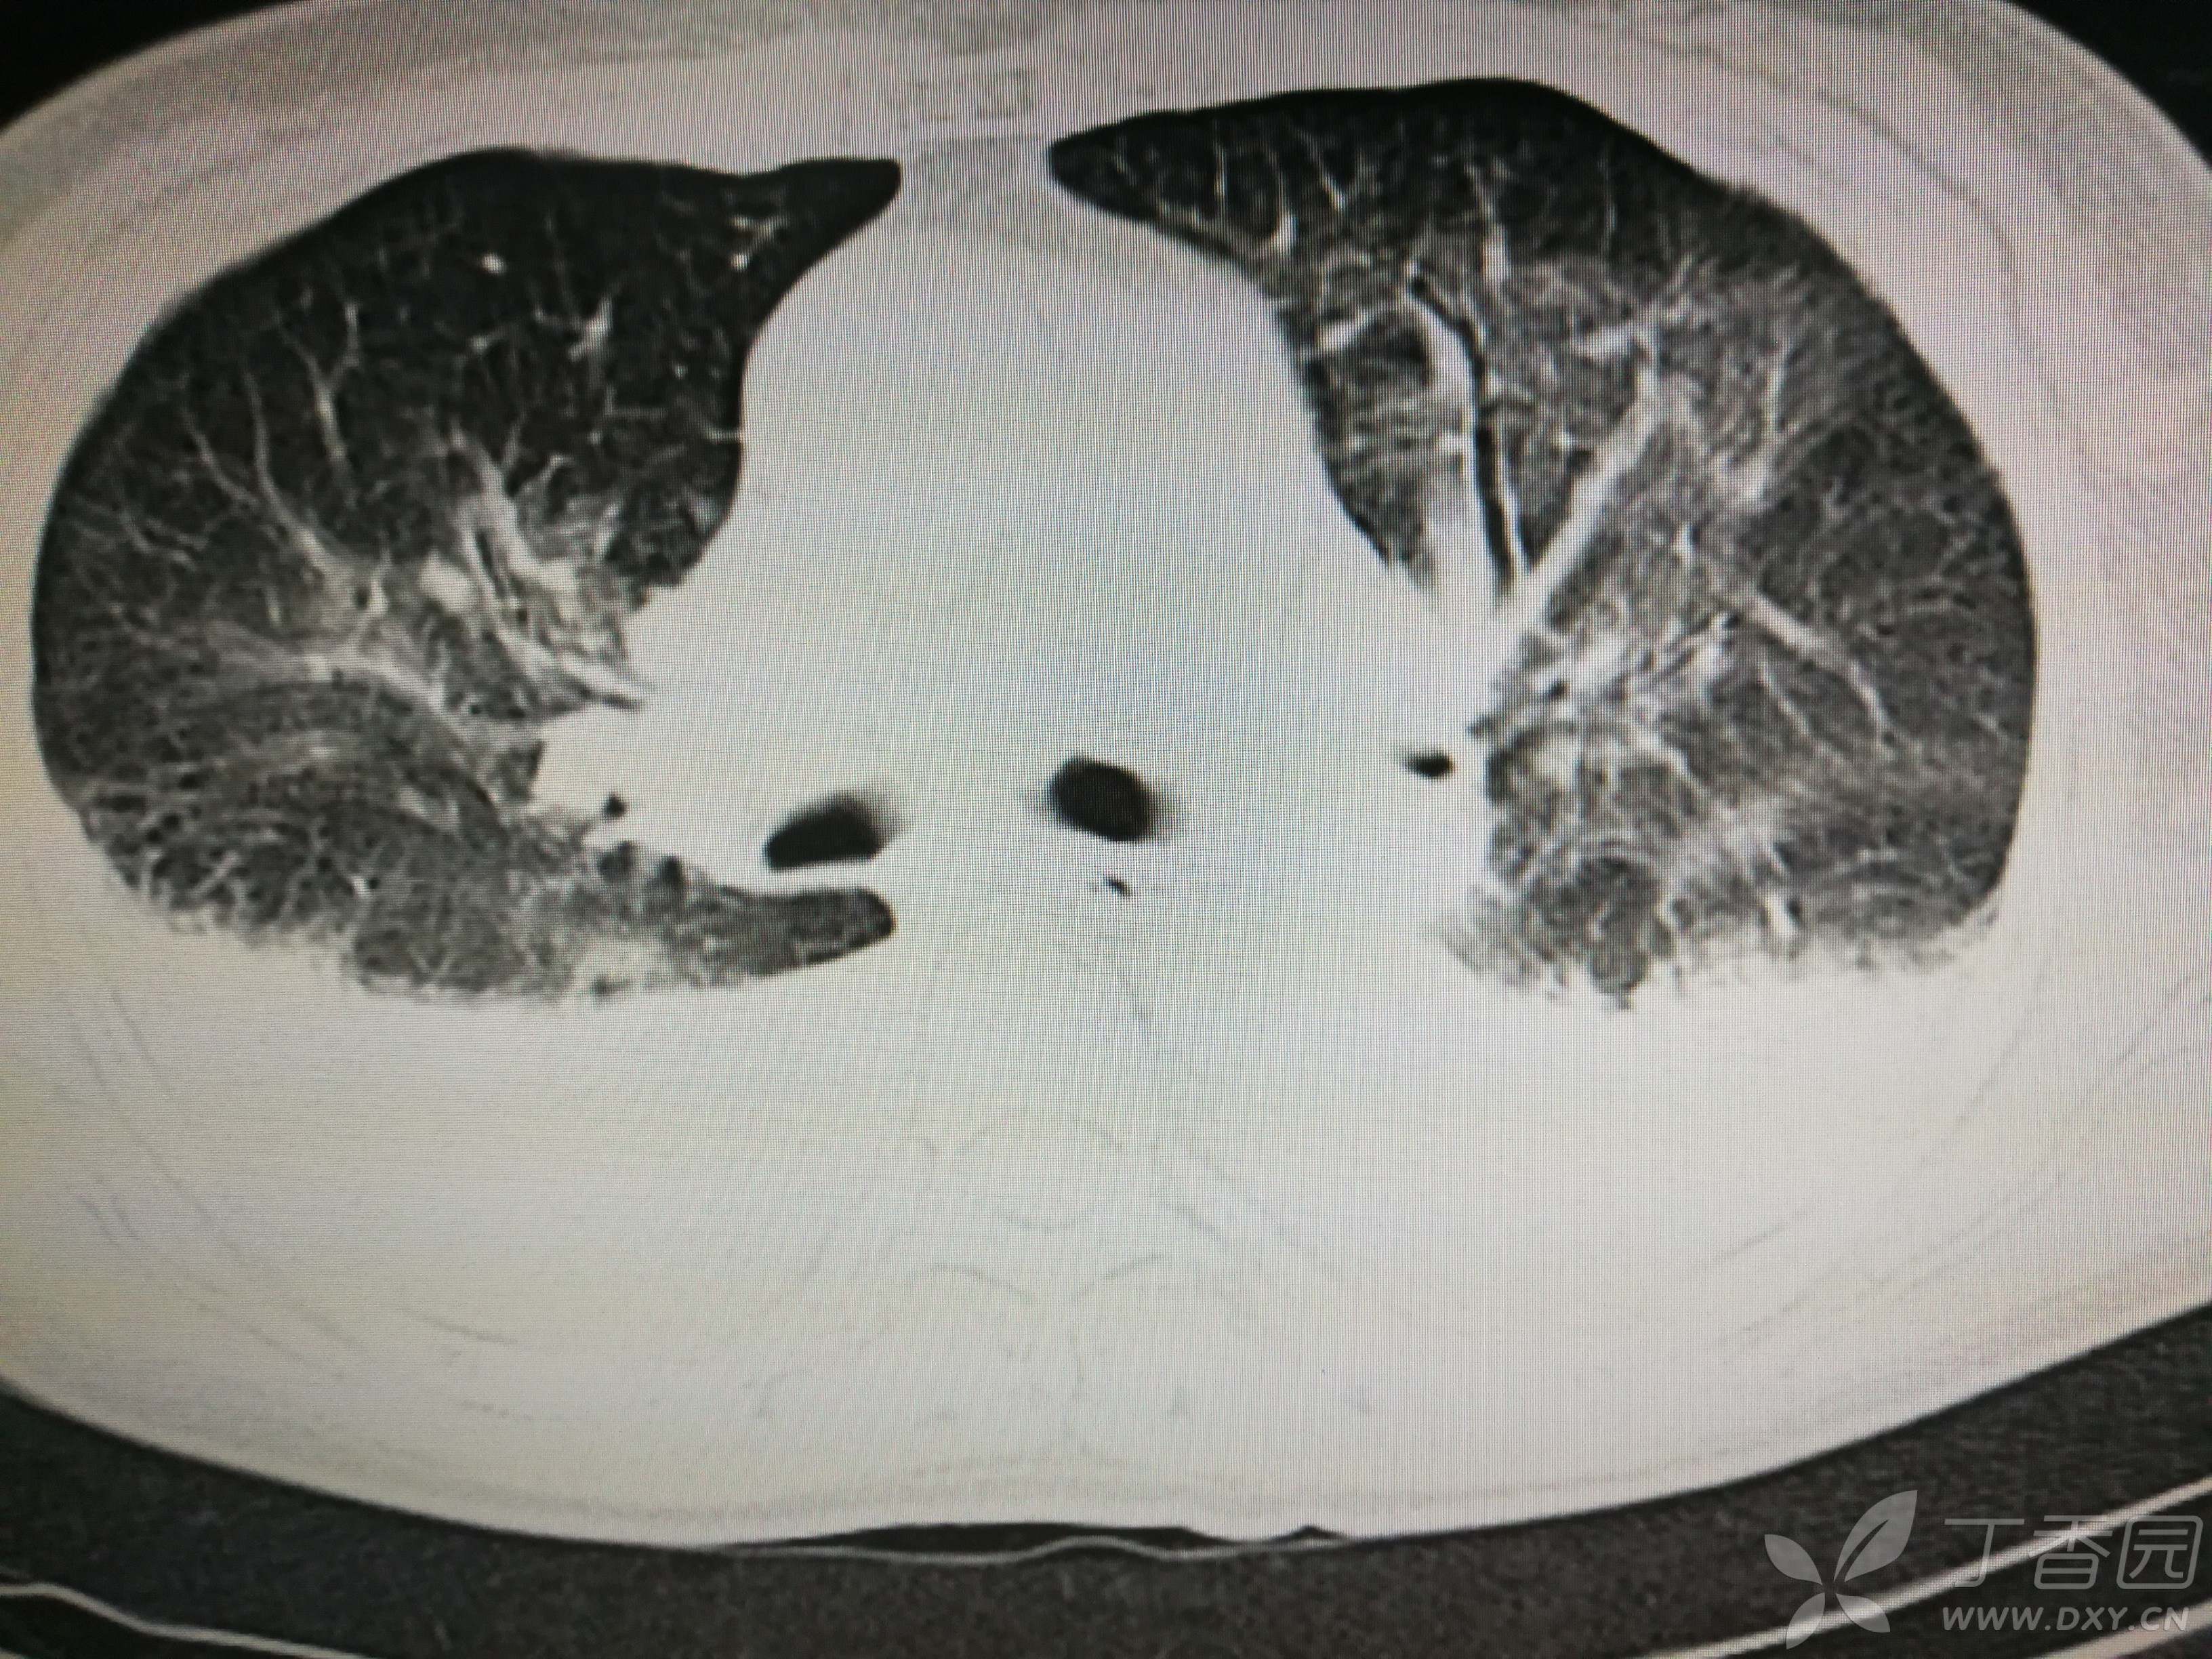

给予低分子肝素钙针抗凝、七叶皂苷钠针消肿及骨牵引固定等等治疗。入院后第四天行“左侧股骨下段骨折切开复位内固定术”(术前查双下肢彩超:双下肢深静脉血流通畅),手术顺利,术后予预防感染、预防血栓形成等治疗。术后患者无明显发热,生命体征平稳。术后第四天复查血常规:白细胞13.4×109/L,血红蛋白84g/L,血小板在正常范围。生化:白蛋白35.7g/L,余无明显异常。当天,患者开始出现轻度胸闷气急,可耐受。术后第五天患者胸闷气急加重,无胸痛,无背痛,无咯血,无意识障碍,无头晕头痛,无恶心呕吐等,急查凝血功能:纤维蛋白原降解产物12mg/L,D二聚体4000ug/L,余无明显异常。查动脉血气分析:pH7.52,氧分压62mmHg,二氧化碳分压30mmHg,碱剩余1.8mmol/L,乳酸1.0mm/L,血红蛋白86g/L。查胸部CT见下(先视频后图片):